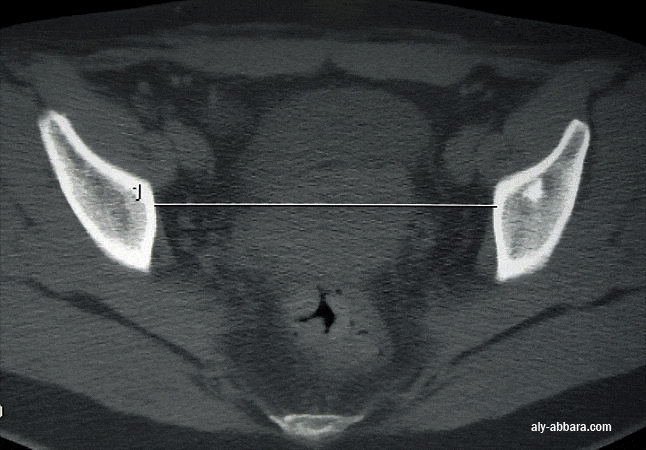

" le détroit supérieur et le diamètre transverse médian "

Le diamètre transverse médian (TM , Scanopelvimétrie) : ou diamètre transverse utile du détroit supérieur ; il est mesuré à mi-distance entre le promontoire et le bord supérieur du pubis.  Valeur normale : en moyenne 125 mm